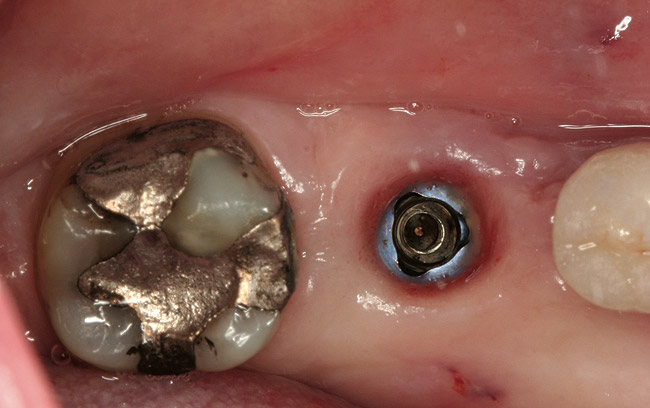

Figure 4  The site following atraumatic implant removal.

Figure 4